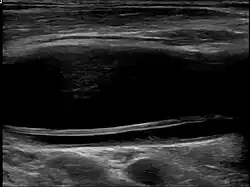

| Dissection in the carotid artery | |

Carotid artery dissection can occur spontaneously or be triggered by trauma, including minor injuries, certain medical conditions, or activities that involve neck movement. It is a leading cause of stroke in young and middle-aged adults. The condition is typically diagnosed through imaging studies, such as ultrasound, magnetic resonance imaging (MRI), magnetic resonance angiography (MRA), or computed tomography angiography (CTA), which help visualize the blood vessels and detect abnormalities.